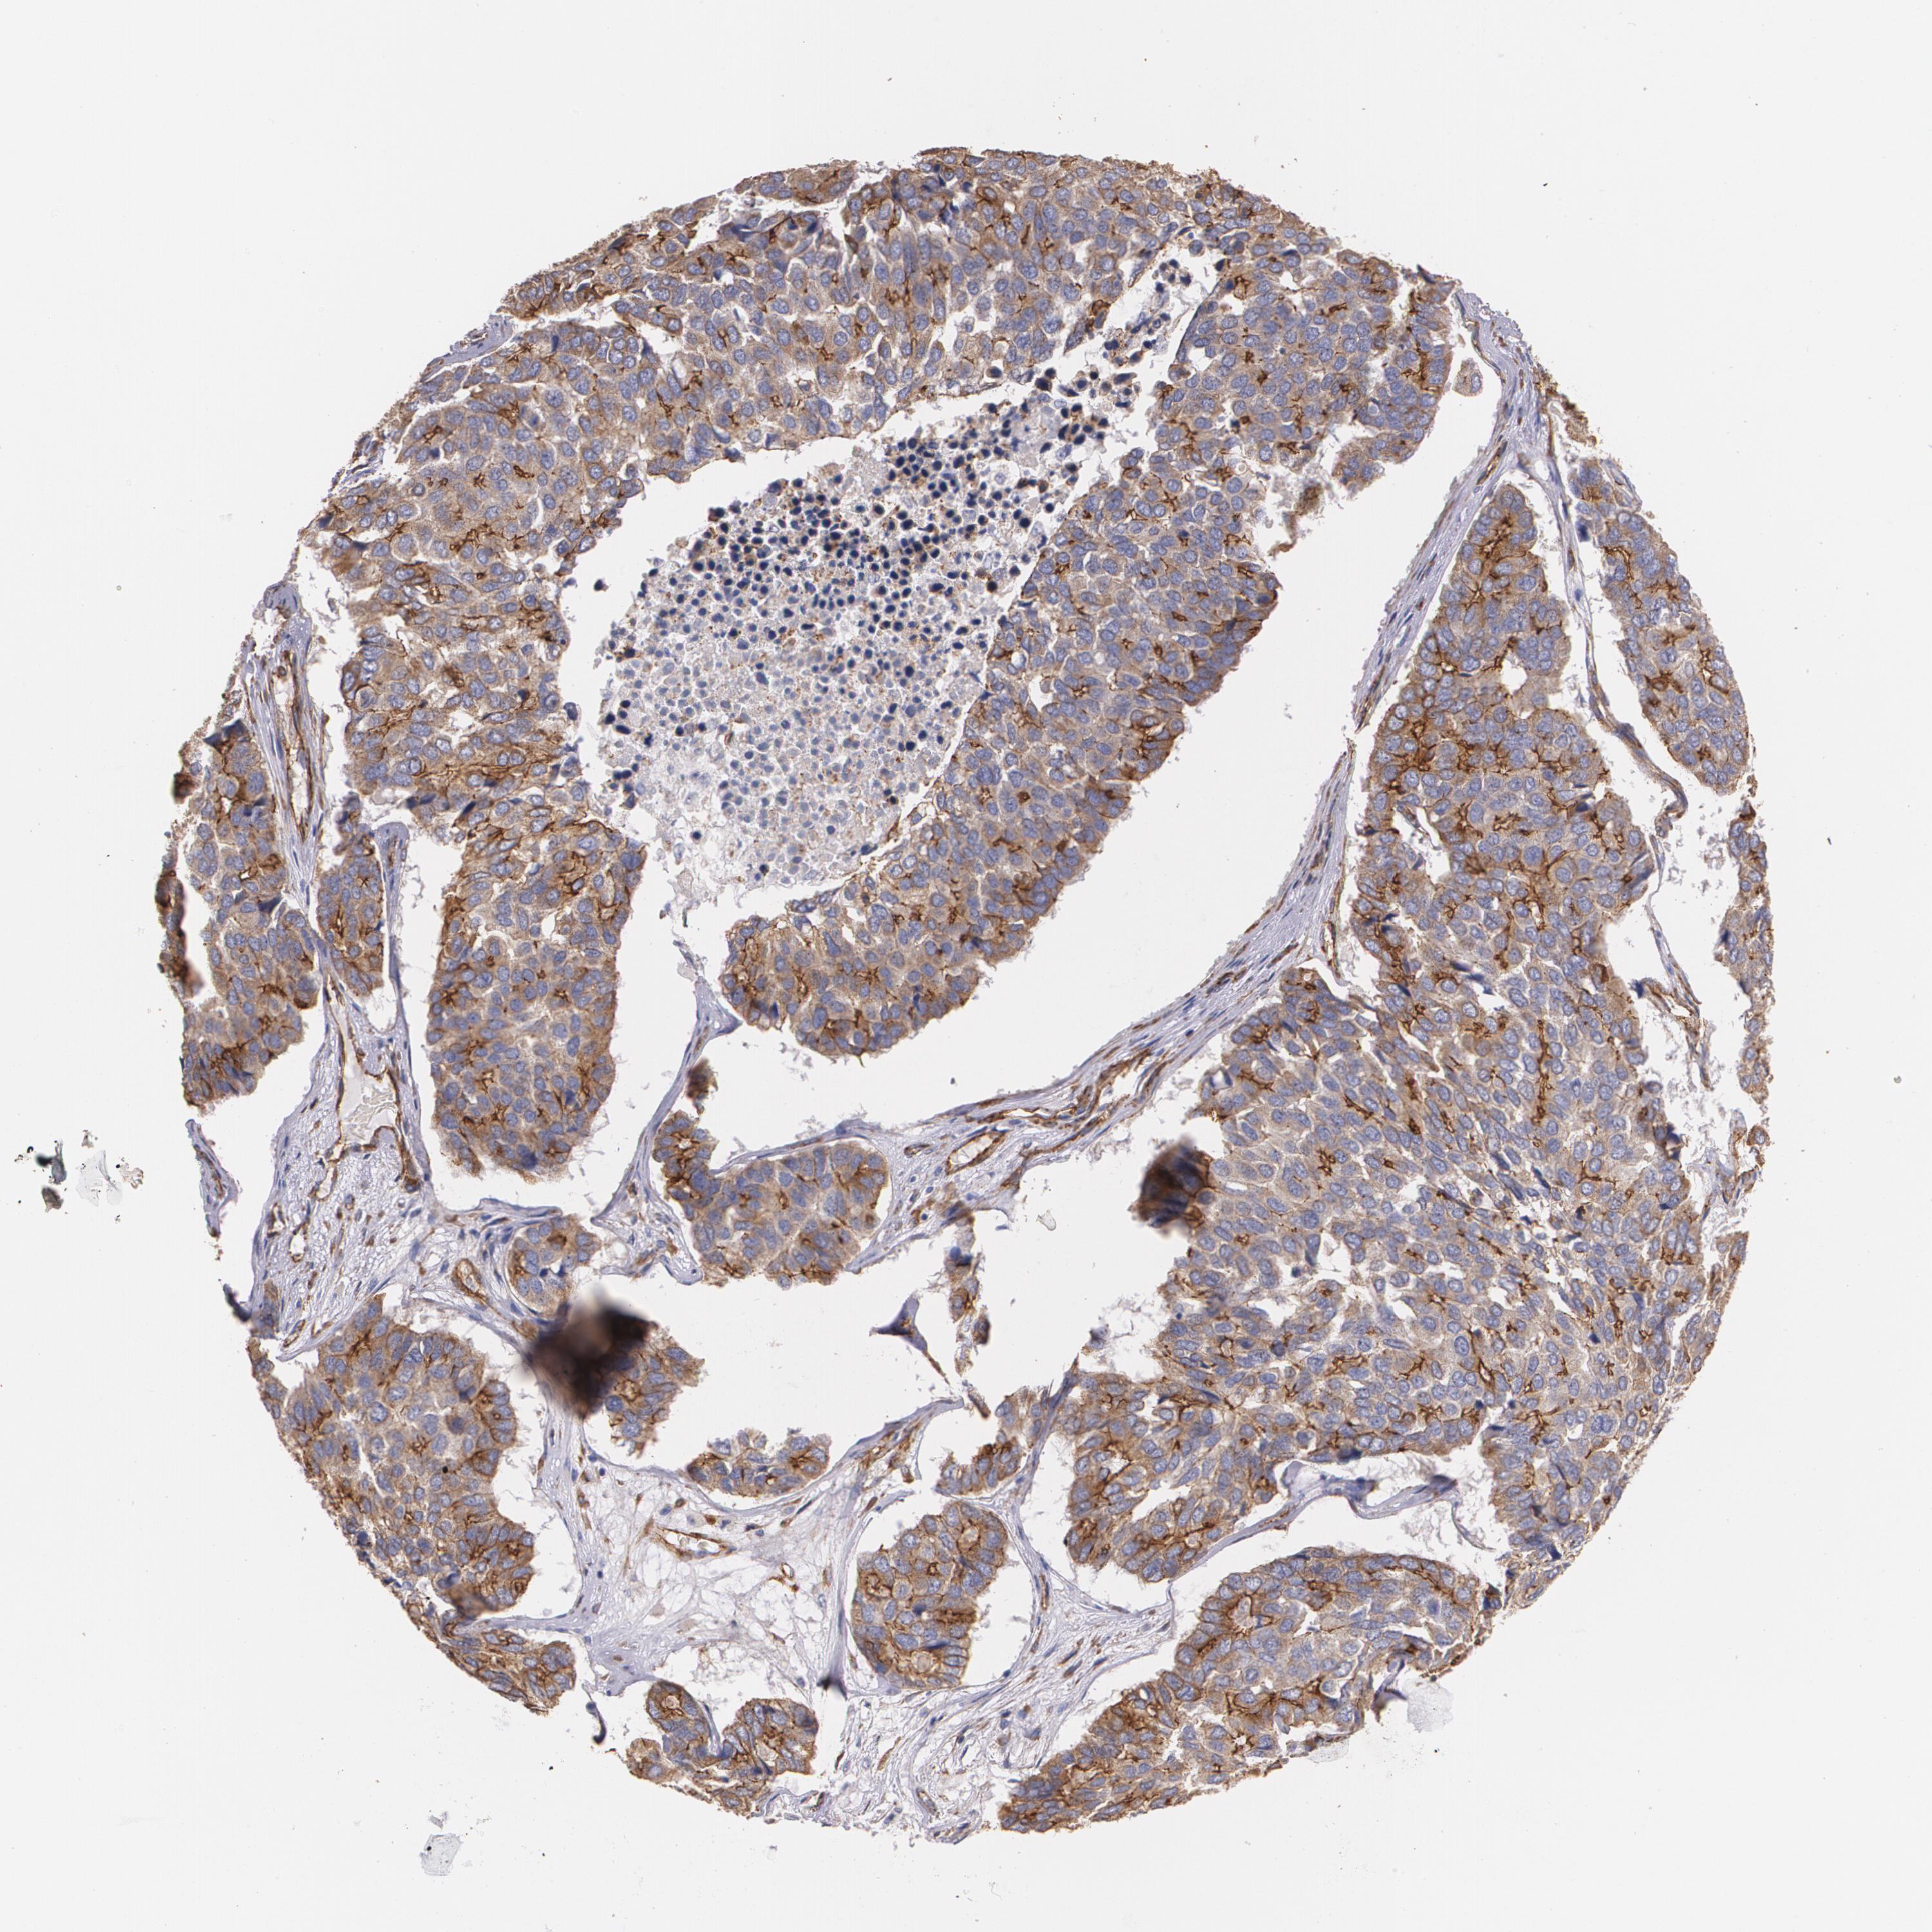

PANCREATIC CANCER - Protein expressioni

A mouse-over function shows sample information and annotation data. Click on an image to view it in a full screen mode. Samples can be filtered based on level of antibody staining by selecting one or several of the following categories: high, medium, low and not detected. The assay and annotation is described here.

Note that samples used for immunohistochemistry by the Human Protein Atlas do not correspond to samples in the TCGA dataset.

Antibody stainingi

Antibody staining in the annotated cell types in the current human tissue is reported as not detected, low, medium, or high, based on conventional immunohistochemistry profiling in selected tissues. This score is based on the combination of the staining intensity and fraction of stained cells.

Each image is clickable and will lead to virtual microscopy that enables deeper exploration of all samples and also displays staining intensity scores, fraction scores and subcellular localization as well as patient and tissue information for each sample.

Antibody HPA001636

Antibody HPA001637

Antibody CAB010822

Adenocarcinoma, NOS

Adenocarcinoma, metastatic, NOS